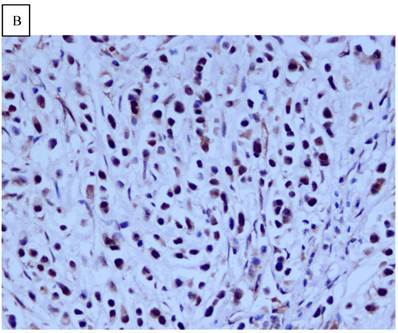

DJ-1 expression in GC was mostly cytoplasmic with some nuclear and membranous staining (Fig.1A and Fig.1B). High DJ-1 was expressed in 66.7% (76/114) of GCs. The immunostaining pattern of PTEN was also characterized by cytoplasmic and nuclear staining of the carcinoma (Fig.1C). High PTEN expression was detected in 41.2% (47/114) of carcinomas, while downregulation or loss of PTEN expression was found in most of GCs (58.7%, 67/114) (Fig.1D). Table 1 shows the correlation between markers analyzed and clinically important histopathological features of the tumors. The higher expression of DJ-1 was significantly correlated with the deeper tumor (P=0.003), lymph node metastasis (p=0.011), distant metastasis (P=0.001) and advanced clinical stage (P=0.001). However, loss expression of PTEN was only found to correlated with distant metastasis (P=0.001) and advanced clinical stage (P=0.018). Furthermore, High DJ-1 expression in tumor cells correlated negatively with downregulation or loss expression of PTEN in tumor (P=0.001).

Fig 1

Immunohistochemical staining of GC tissue microarray. (a) High expression of DJ-1 in the cytoplasm of tumor cells was shown under lower power field. (b) In some GCs, nuclear and cytoplasmic positive staining of DJ-1 in the tumor cells could be also observed. (c) High expression of PTEN could be found in tumor cells of some GCs, while, the adjacent non-neoplastic glands (circled with dotted line) showed strongly and diffusely positive staining of PTEN in cytoplasm and nuclear. (d) However, in most of GCs, PTEN expression was entirely loss or remarkably reduced. (a and d, immunohistochemical staining with original magnification ×100; b and c, immunohistochemical staining with original magnification ×400).